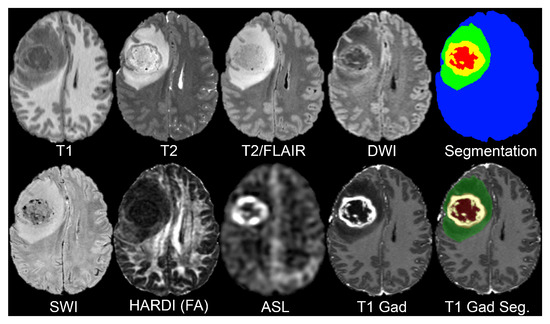

For this study, we used the UCSF Preoperative Diffuse Glioma MRI (UCSF-PDGM) dataset [14], which is publicly available through The Cancer Imaging Archive (TCIA) [15]. The dataset consists of preoperative multimodal MRI scans from 495 adult patients with histopathologically confirmed diffuse gliomas (WHO grades II–IV). All scans were acquired at UCSF using a standardized 3 Tesla MRI protocol between 2015 and 2021 (see Figure 1).

This dataset includes a comprehensive collection of MRI sequences, each offering unique insights into the brain structure and pathology (see Table 1). The T1-weighted scans, both pre- and post-contrast, provide detailed anatomical information and help delineate the tumor’s structural boundaries and contrast-enhancing regions. T2-weighted imaging highlights fluid content and edema, making it useful for identifying the surrounding tissue changes. T2/FLAIR (Fluid-Attenuated Inversion Recovery) suppresses cerebrospinal fluid (CSF) signals, enhancing the visibility of peritumoral lesions and infiltrative edema often missed in standard T2 scans.

In order to capture microstructural tissue properties, the dataset includes Diffusion-Weighted Imaging (DWI) as it assesses the motion of water molecules, and is often employed to evaluate the cellular density within the tumor. Susceptibility-weighted imaging (SWI) detects blood products, calcifications, and other vascular abnormalities found in high-grade gliomas as it is sensitive to magnetic field variation and can detect these areas.

Tumor perfusion is assessed with Arterial Spin Labeling (ASL) as a non-contrast perfusion imaging method and, thus, obtains functional imaging. The dataset also contains High Angular Resolution Diffusion Imaging (HARDI) with 55 diffusion directions, which allows for more sophisticated diffusion modeling to evaluate white matter integrity, and analyze the patterns of tumor infiltration more precisely.

Lastly, segmentation maps are given for each subject to determine areas of tumors and provide anatomical landmarks for model training and assessment. These maps are critical for localizing regions of interest pertaining to the disease across different modalities and ensuring standardized preprocessing.

This variety of imaging data is what sustains our research investigation and supports the study with an automated assessment of MRI-derived mortality predictors in glioma patients on a per-modality basis.

Figure 1. The University of California San Francisco Preoperative Diffuse Glioma MRI Adapted with permission from Ref. [14]. Copyright 2022 Calabrese et al.